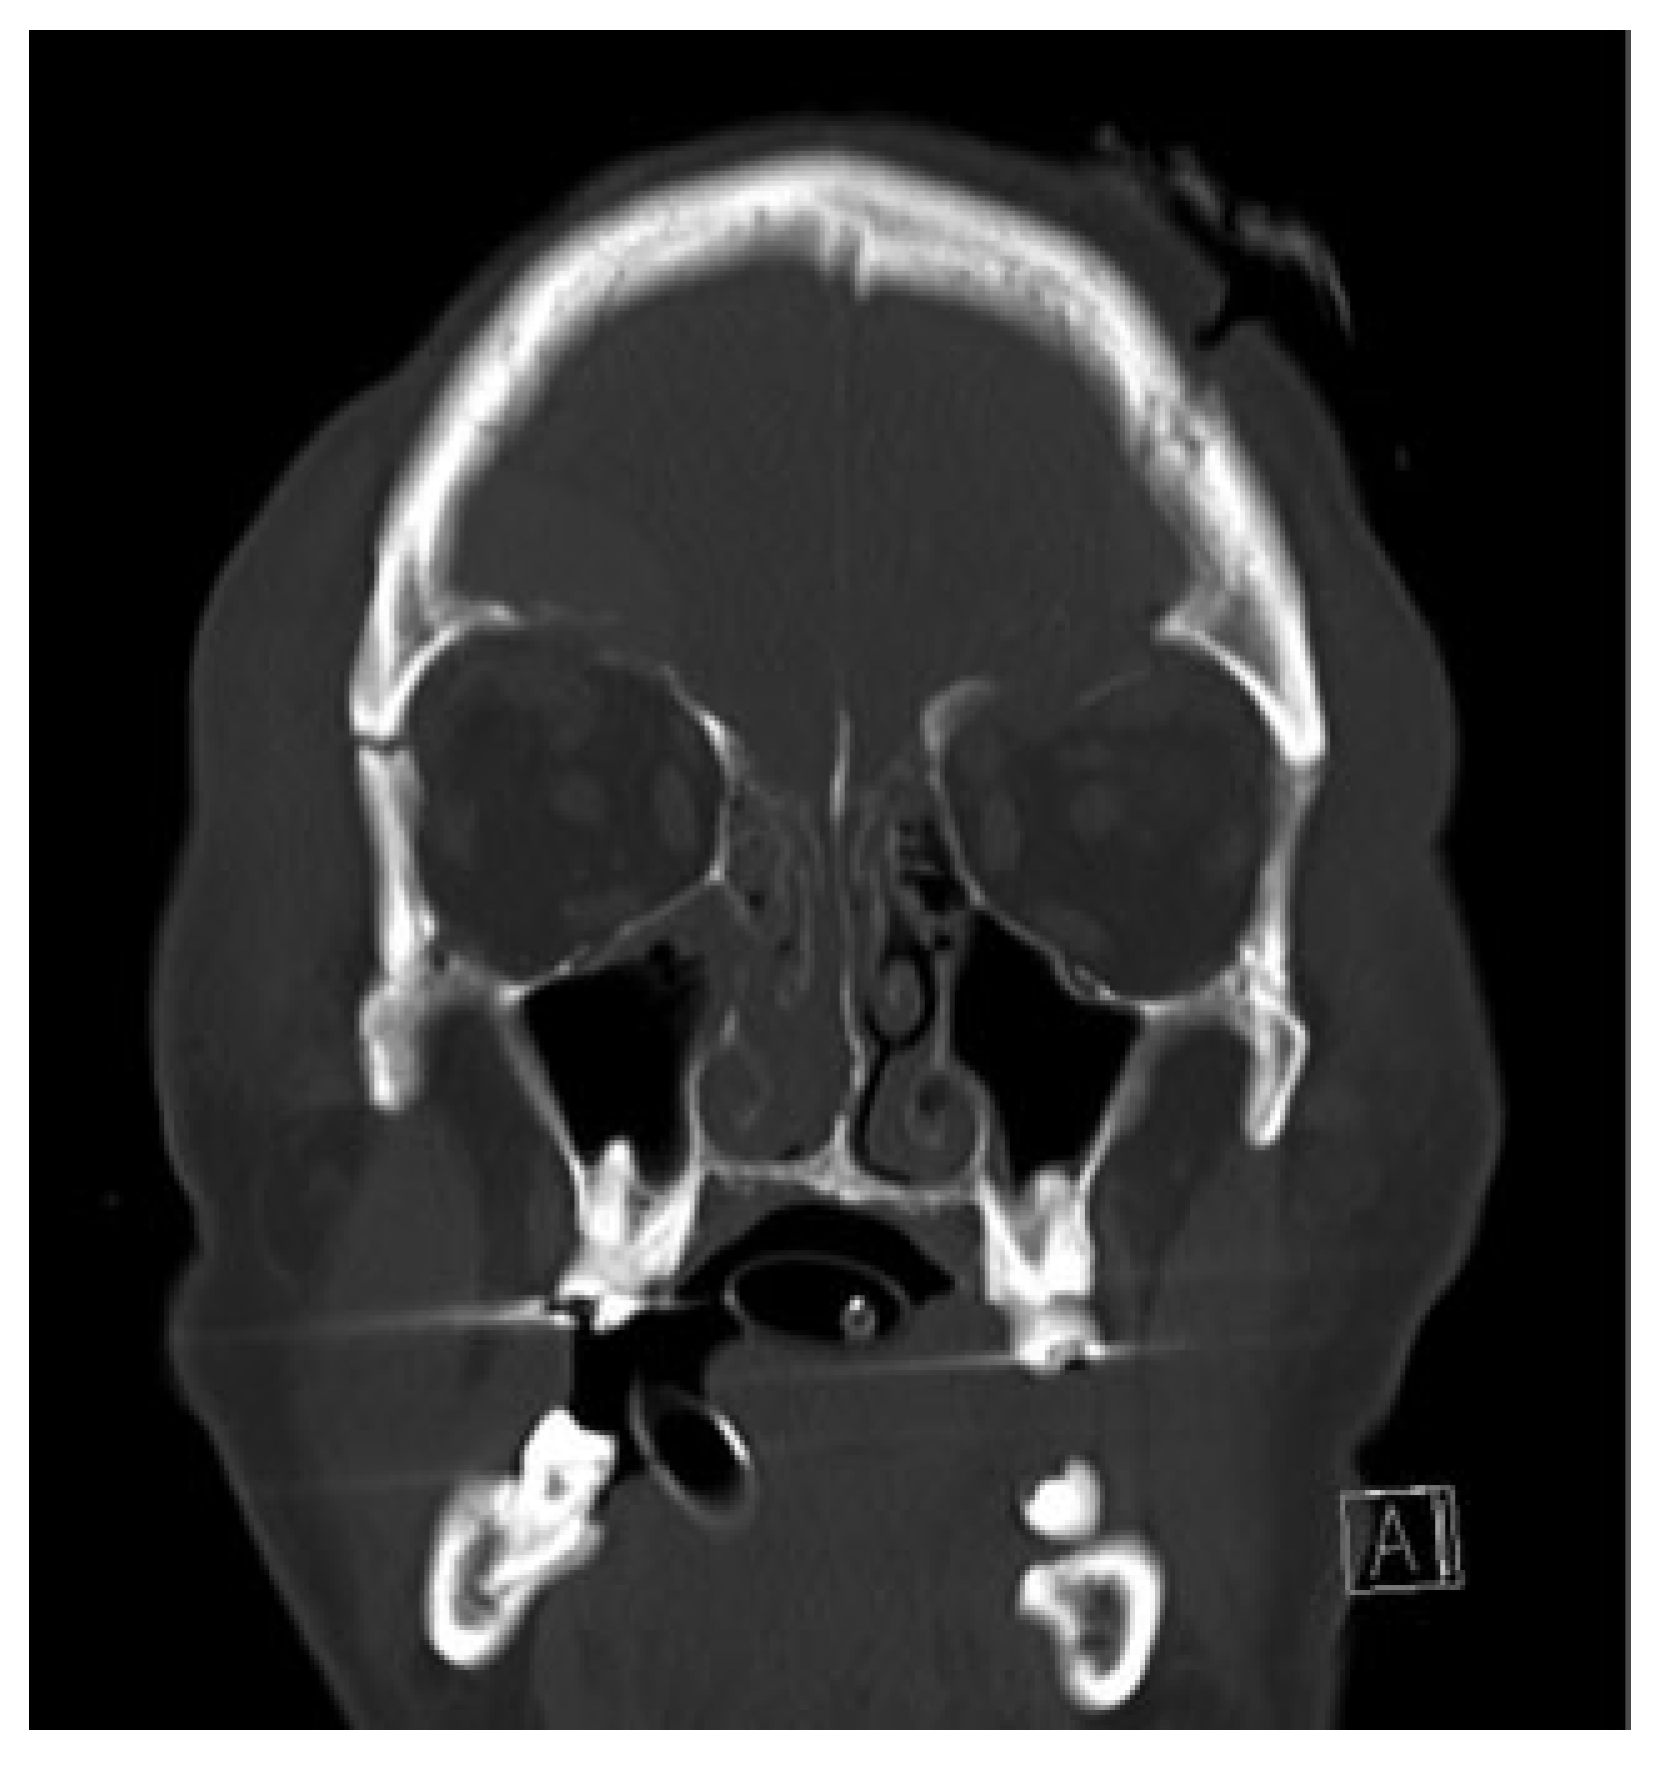

The diagnosis, while it can be inferred on clinical examination, is confirmed with radiology, preferably computed tomography (CT) of all facial bones (Figure 1). Other imaging modalities including MRI for fine examination of extraocular muscles or neural/cerebral involvement may be used.

Figure 1. Computed tomography demonstrating an orbital roof fracture.